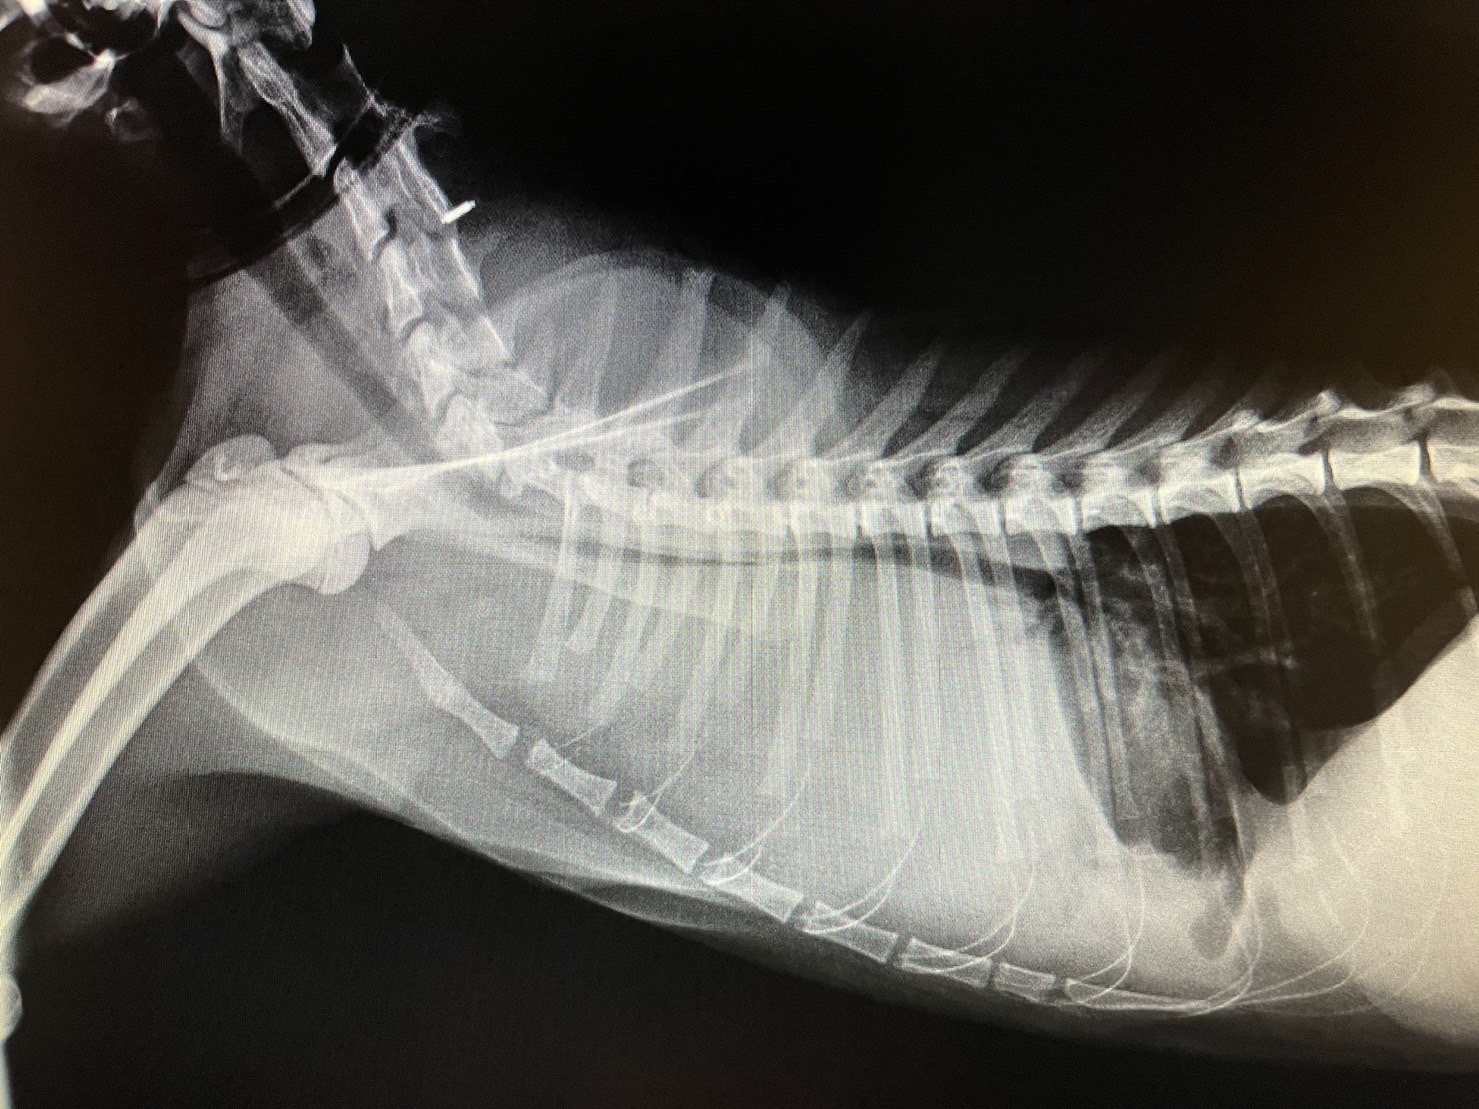

一般我們將胸腔內的積液統稱為胸水,

在以下幾個狀況可能產生:

1.罹患心血管疾病的動物。

2.胸腔內的器官破裂出血時發生胸腔積血,常見於車禍、

墜樓以及胸腔內腫瘤破裂的動物。

3.胸腔內細菌感染造成化膿性液體蓄積,稱為膿胸。

4.腫瘤造成積液,可能為原發性或是身上其他處腫瘤轉移至胸腔。

5.乳糜胸,胸管擴張或破裂導致,通常發生於年輕動物。

胸水的成因有很多種,一旦發現胸水,需要抽出胸腔內液體,

不但可以緩解動物呼吸困難的狀況,

最重要的是可將液體進行分析,視情況需同時進行其他全身檢查,

例如血液學檢查、X光檢查、超音波檢查…,才能找到胸水產生的原因,針對病因進行治療。

若是單純抽出胸水,而沒有找到原因,胸水持續產生會讓動物反覆陷入缺氧的危險當中。